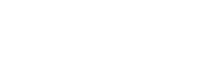

Leczenie rozchwianych zębów – czym jest?

Leczenie rozchwianych zębów to zespół działań mających na celu wzmocnienie zębów, które utraciły swoją stabilność w łuku zębowym. Najczęściej jest to odpowiedź na skutki chorób przyzębia, urazów mechanicznych lub przeciążeń zgryzowych. W zależności od przyczyny i stopnia zaawansowania problemu, stomatolog może zaproponować różne rozwiązania – od terapii wspomagających gojenie dziąseł, przez leczenie przyczynowe choroby przyzębia, aż po tzw. szynowanie, czyli mechaniczne usztywnienie zębów.

Wskazania do leczenia rozchwianych zębów

Leczenie rozchwianych zębów jest konieczne zawsze wtedy, gdy ich ruchomość zaczyna wpływać na codzienne funkcjonowanie – gryzienie, żucie, a nawet mowę.

- Najczęstszym wskazaniem są choroby przyzębia, takie jak paradontoza, które prowadzą do osłabienia struktur utrzymujących ząb w zębodole.

- Problem może pojawić się także po silnym urazie mechanicznym – np. w wyniku wypadku lub przeciążenia zgryzowego – gdy ząb traci swoją stabilność.

- Innym powodem są zaburzenia okluzji, czyli niewłaściwy kontakt między zębami górnymi i dolnymi, które z czasem prowadzą do mikrourazów i rozchwiania.

Jak przebiega leczenie rozchwianych zębów?

Zanim lekarz przystąpi do właściwego leczenia, kluczowe jest poznanie przyczyny rozchwiania – to ona decyduje o dalszym postępowaniu.

Proces zazwyczaj rozpoczyna się od diagnostyki, która obejmuje m.in. ocenę stanu przyzębia, zdjęcie RTG oraz dokładny wywiad z pacjentem.

Kolejny krok to eliminacja czynników sprzyjających pogłębianiu się problemu – może to być oczyszczenie zębów z kamienia, leczenie stanu zapalnego dziąseł, a nawet korekta zgryzu.

Jedną z najczęściej stosowanych metod jest tzw. szynowanie, czyli stabilizacja rozchwianych zębów za pomocą cienkiej taśmy z włókna szklanego lub materiału kompozytowego. Szyna zakładana jest zazwyczaj po wewnętrznej stronie zębów, co sprawia, że jest niemal niewidoczna. Cały zabieg jest bezbolesny i trwa kilkanaście minut, a jego efektem jest zauważalna poprawa komfortu pacjenta – zęby przestają się ruszać, a ryzyko ich utraty znacząco się zmniejsza.

Leczenie rozchwianych zębów – czy warto?

Zdecydowanie tak. Leczenie rozchwianych zębów to często ostatnia szansa na uratowanie naturalnego uzębienia bez konieczności jego usuwania. W wielu przypadkach pozwala nie tylko ustabilizować zęby, ale też zahamować postęp choroby przyzębia, poprawić komfort życia i przywrócić pewność siebie podczas mówienia czy uśmiechania się.